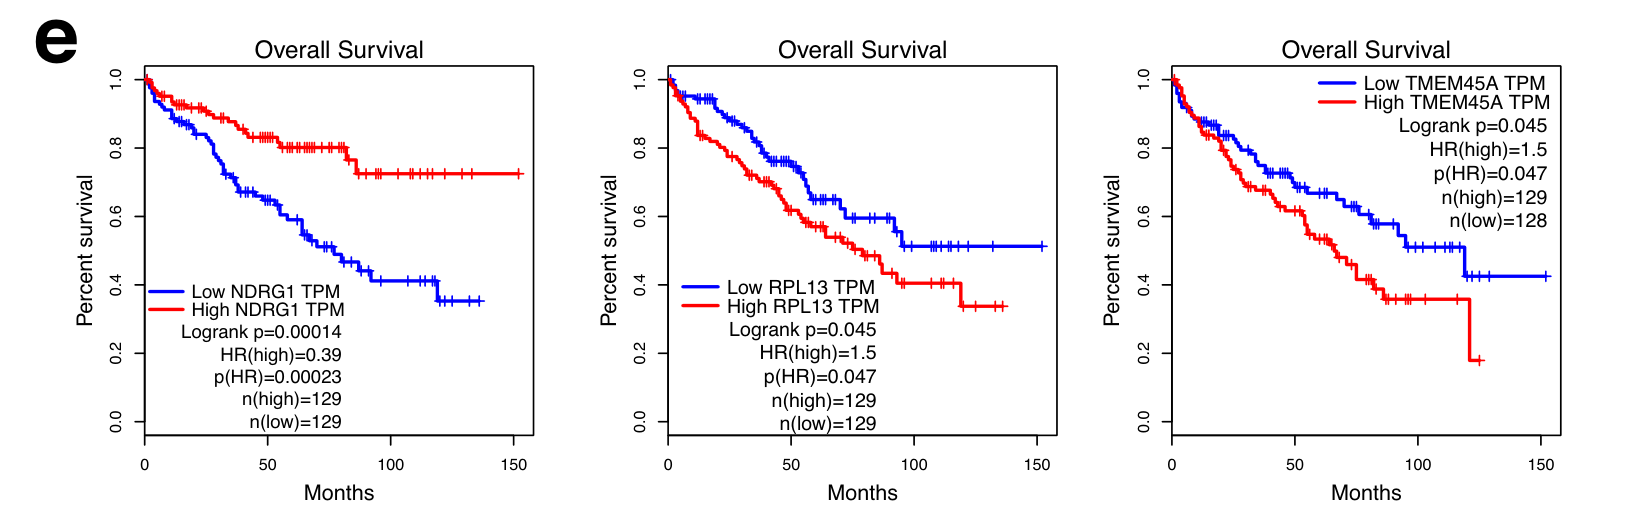

Aggarwal B. and Sinha S. - 2025

CellSP enables module discovery and visualization for subcellular spatial transcriptomics data

Condition Dimension

N/A

Data Components

Evaluation metrics

Data

Modality

Imaging-based

Resolution of observation

Sub-cellular

Visualized Elements

FeatureObservation

Biological

CellularMolecularTissue

Abstraction

None

Chart Type

ScatterplotSpatial Gene Expression Map

Communicative/Contextualization

AnnotationHighlighting

Comparative Design

None

Layout

Spatial : Physical

What is the raw visual evidence for the subcellular localization of the module genes within individual cells?